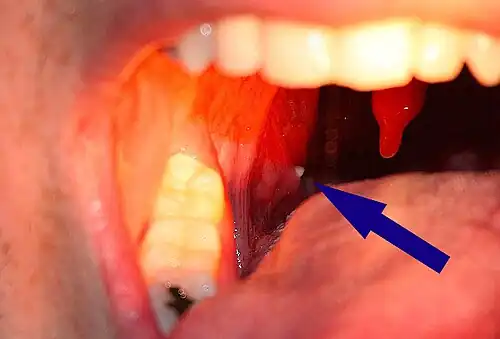

| A tonsillolith lodged in the tonsillar crypt | |

Tonsil stones, also known as tonsilloliths, are mineralizations of debris within the crevices of the tonsils.[1][3] When not mineralized, the presence of debris is known as chronic caseous tonsillitis (CCT).[1] Symptoms may include bad breath,[1] foreign body sensation, sore throat, pain or discomfort with swallowing, and cough.[4] Generally there is no pain, though there may be the feeling of something present.[1] The presence of tonsil stones may be otherwise undetectable; however, some people have reported seeing white material in the rear of their throat.

Tonsilloliths or tonsil stones are calcifications that form in the crypts of the palatal tonsils. They are also known to form in the throat and on the roof of the mouth. Tonsils are filled with crevices where bacteria and other materials, including dead cells and mucus, can become trapped. When this occurs, the debris can become concentrated in white formations that occur in the pockets.[12] Researchers found aerobic bacteria present on the surface of tonsilloliths and anaerobic bacteria at the core of tonsilloliths. They have the potential to cause oral halitosis as they contain volatile sulfur compounds and sulfur derived gases, foul smelling compounds produced during bacterial metabolism.[16] Tonsilloliths are formed when this trapped debris accumulates and are expressed from the tonsil. They are generally soft, sometimes rubbery. This tends to occur most often in people who suffer from chronic inflammation in their tonsils or repeated bouts of tonsillitis.[12] They are often associated with post-nasal drip.